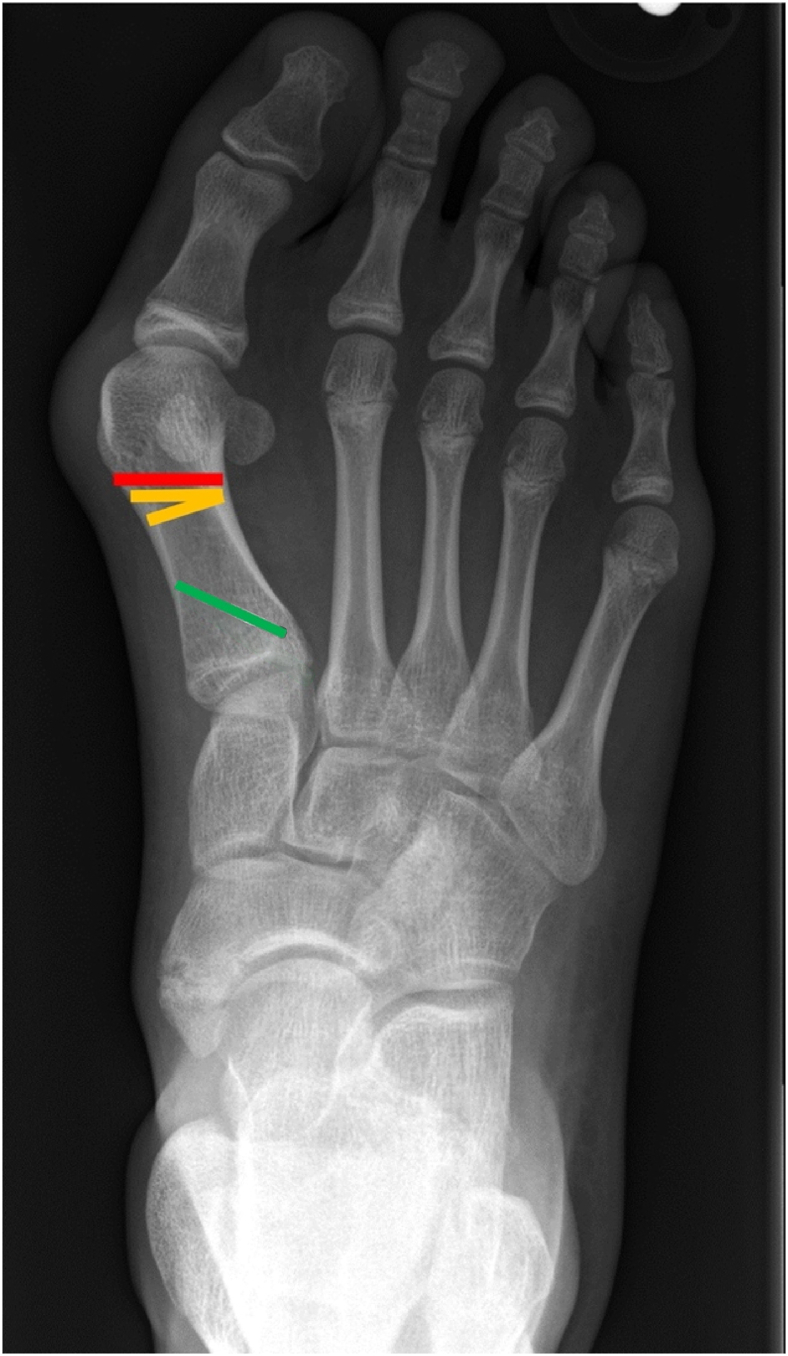

Abstract Image